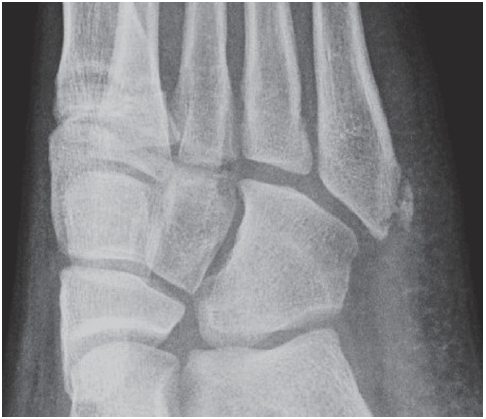

다음은 제5중족골 골절의 네 가지 방사선 영상이다. 손상은 무엇인가?

제5중족골 기저부 골절 (Fractures of the Fifth Metatarsal Base)

① 족저근막의 외측열 부착부의 견열 골절

② 단비골건 부착부의 견열 골절

③ 존스 골절(Jones fracture)

제5중족골 감입 골절(impaction fracture)로, 피로 골절으로 종종 시작된다.

④ 손상 부위 없음

이는 제5중족골 기저부의 정상적인 발달성 골돌기(apophysis)에 해당한다.